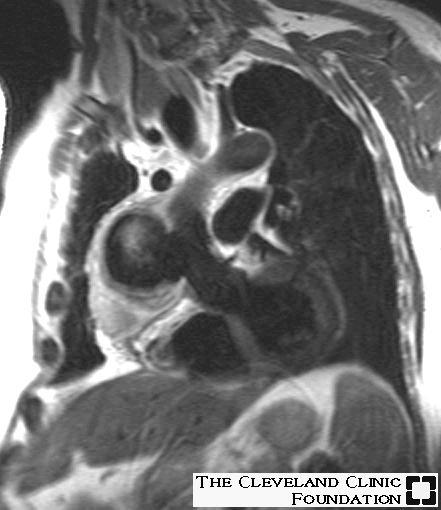

Monitoring cardiac sarcoidosis with MRI could save lives

At the 2002 European Congress of Radiology in Vienna, Dr. Olivier Vignaux from Hôpital Cochin and the University of Paris in France discussed his group's study of cardiac sarcoidosis. The group concluded that more frequent monitoring with MRI could save lives.